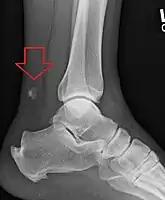

Radiography can also be used to indirectly identify Achilles tears. Radiography uses X-rays to analyse the point of injury. This is not very effective at identifying injuries to soft tissue. X-rays are created when high energy electrons hit a metal source. X-ray images are acquired by utilising the different attenuation characteristics of dense (e.g. calcium in bone) and less dense (e.g. muscle) tissues when these rays pass through tissue and are captured on film. X-rays are generally exposed to optimise visualisation of dense objects such as bone while soft tissue remains relatively undifferentiated in the background. Radiography has little role in assessment of Achilles' tendon injury and is more useful for ruling out other injuries such as calcaneal fractures.[13]

Achilles tendon avulsion seen on plain X-ray